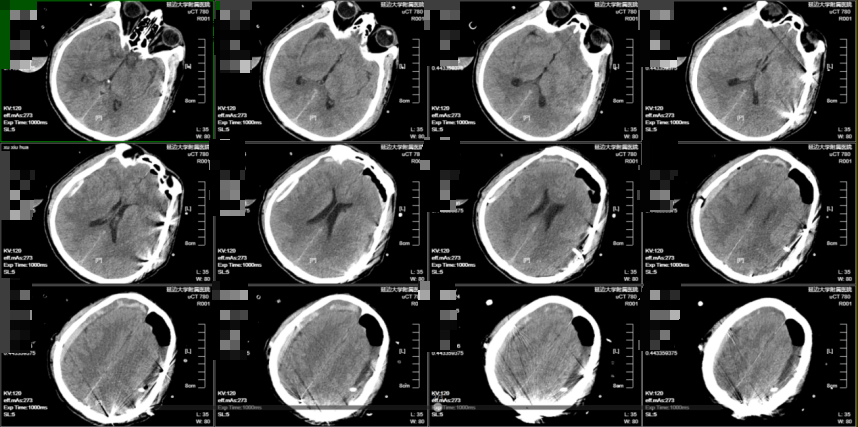

病例二:

65岁男性患者,头痛头晕伴右侧肢体活动不灵约3天。头部CT示双侧额顶部慢性硬膜下血肿。黄宪主任医师、马吉男主治医师团队先行经导管脑膜中动脉(MMA)栓塞术,术中造影显示异常增生血管消失。接台行双侧颅骨钻孔引流术,术中见血肿量明显减少。术后恢复顺利,头痛消失,肌力改善,随访当地医院头部CT示无复发。

图5经导管脑膜中动脉(MMA)栓塞术+钻孔引流术后